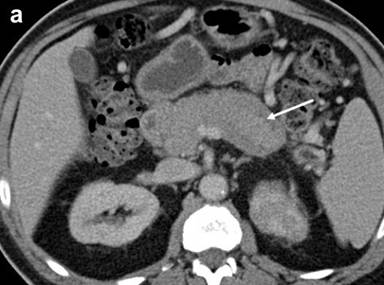

The patient was referred to our institution for consultation where he underwent repeat multiplanar MDCT with the use of 100 mL intravenous (iopromide; Ultravist® 300, Bayer, NJ, USA) contrast material delivered at 3 mL/s and imaged with a 70 s delay. Nine hundred mL oral (water) contrast was also utilized. Images were obtained at 120 kVp and 200 mAs and reconstructed at 5 mm. The pancreas was universally enlarged with a distinct rim of hypoattenuation (Figure 1). The wall of the gastric body and fundus, predominantly posteriorly, was diffusely thickened, measuring up to 1.4 cm, and had a nodular appearance (Figure 1). The gastric wall thickening spared the antrum. No hyperenhancement of the gastric wall was noted. There were additionally noted several hypodense lesions in both kidneys that were surrounded by hypovascular soft tissue (Figure 1) as well as focal jejunal wall thickening without hyperenhancement (Figure 1).

Figure 1. a. Axial MDCT image of the abdomen with intravenous and oral contrast demonstrates a thickened, “sausage-like” pancreas with a hypodense rim of tissue (arrow). b. Axial MDCT image of the abdomen with intravenous and oral contrast demonstrates a thickened and nodular appearance of the stomach wall at the level of the gastric body measuring up to 1.4 cm (arrow). c. Sagittally reformatted MDCT image of the abdomen shows the thickened and nodular gastric body wall, most pronounced posteriorly (arrow). d. Axial MDCT image demonstrates bilateral renal lesions (arrows) with a soft tissue attenuation within and immediately adjacent to the left kidney (dotted arrow). e. Axial MDCT image demonstrates focal jejunal wall thickening. |